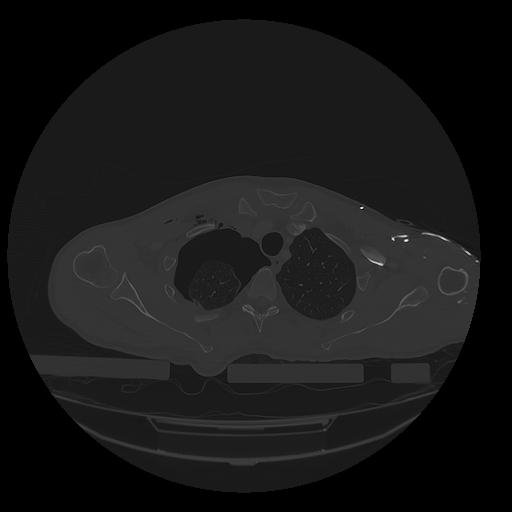

31 PULMON,CE,Vol,1.0,PULMON,,